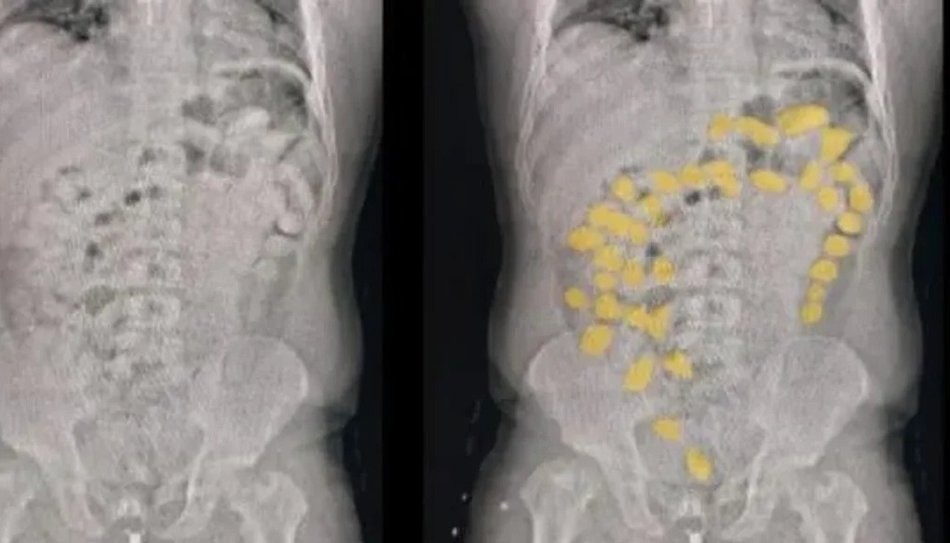

Mientras realizaban las actuaciones, notaron que dos ciudadanos bolivianos habían estallado en una crisis de nervio. Después de una conversación, uno de los sospechosos confirmó que habían consumido unas 187 cápsulas de cocaína. Inmediatamente fueron trasladados hacia la capital santiagueña para que iniciaran el proceso de evacuación y después se concretara su procesamiento. Los especialistas estiman que en el interior de sus cuerpos podrían tener hasta dos kilos de esa sustancia.